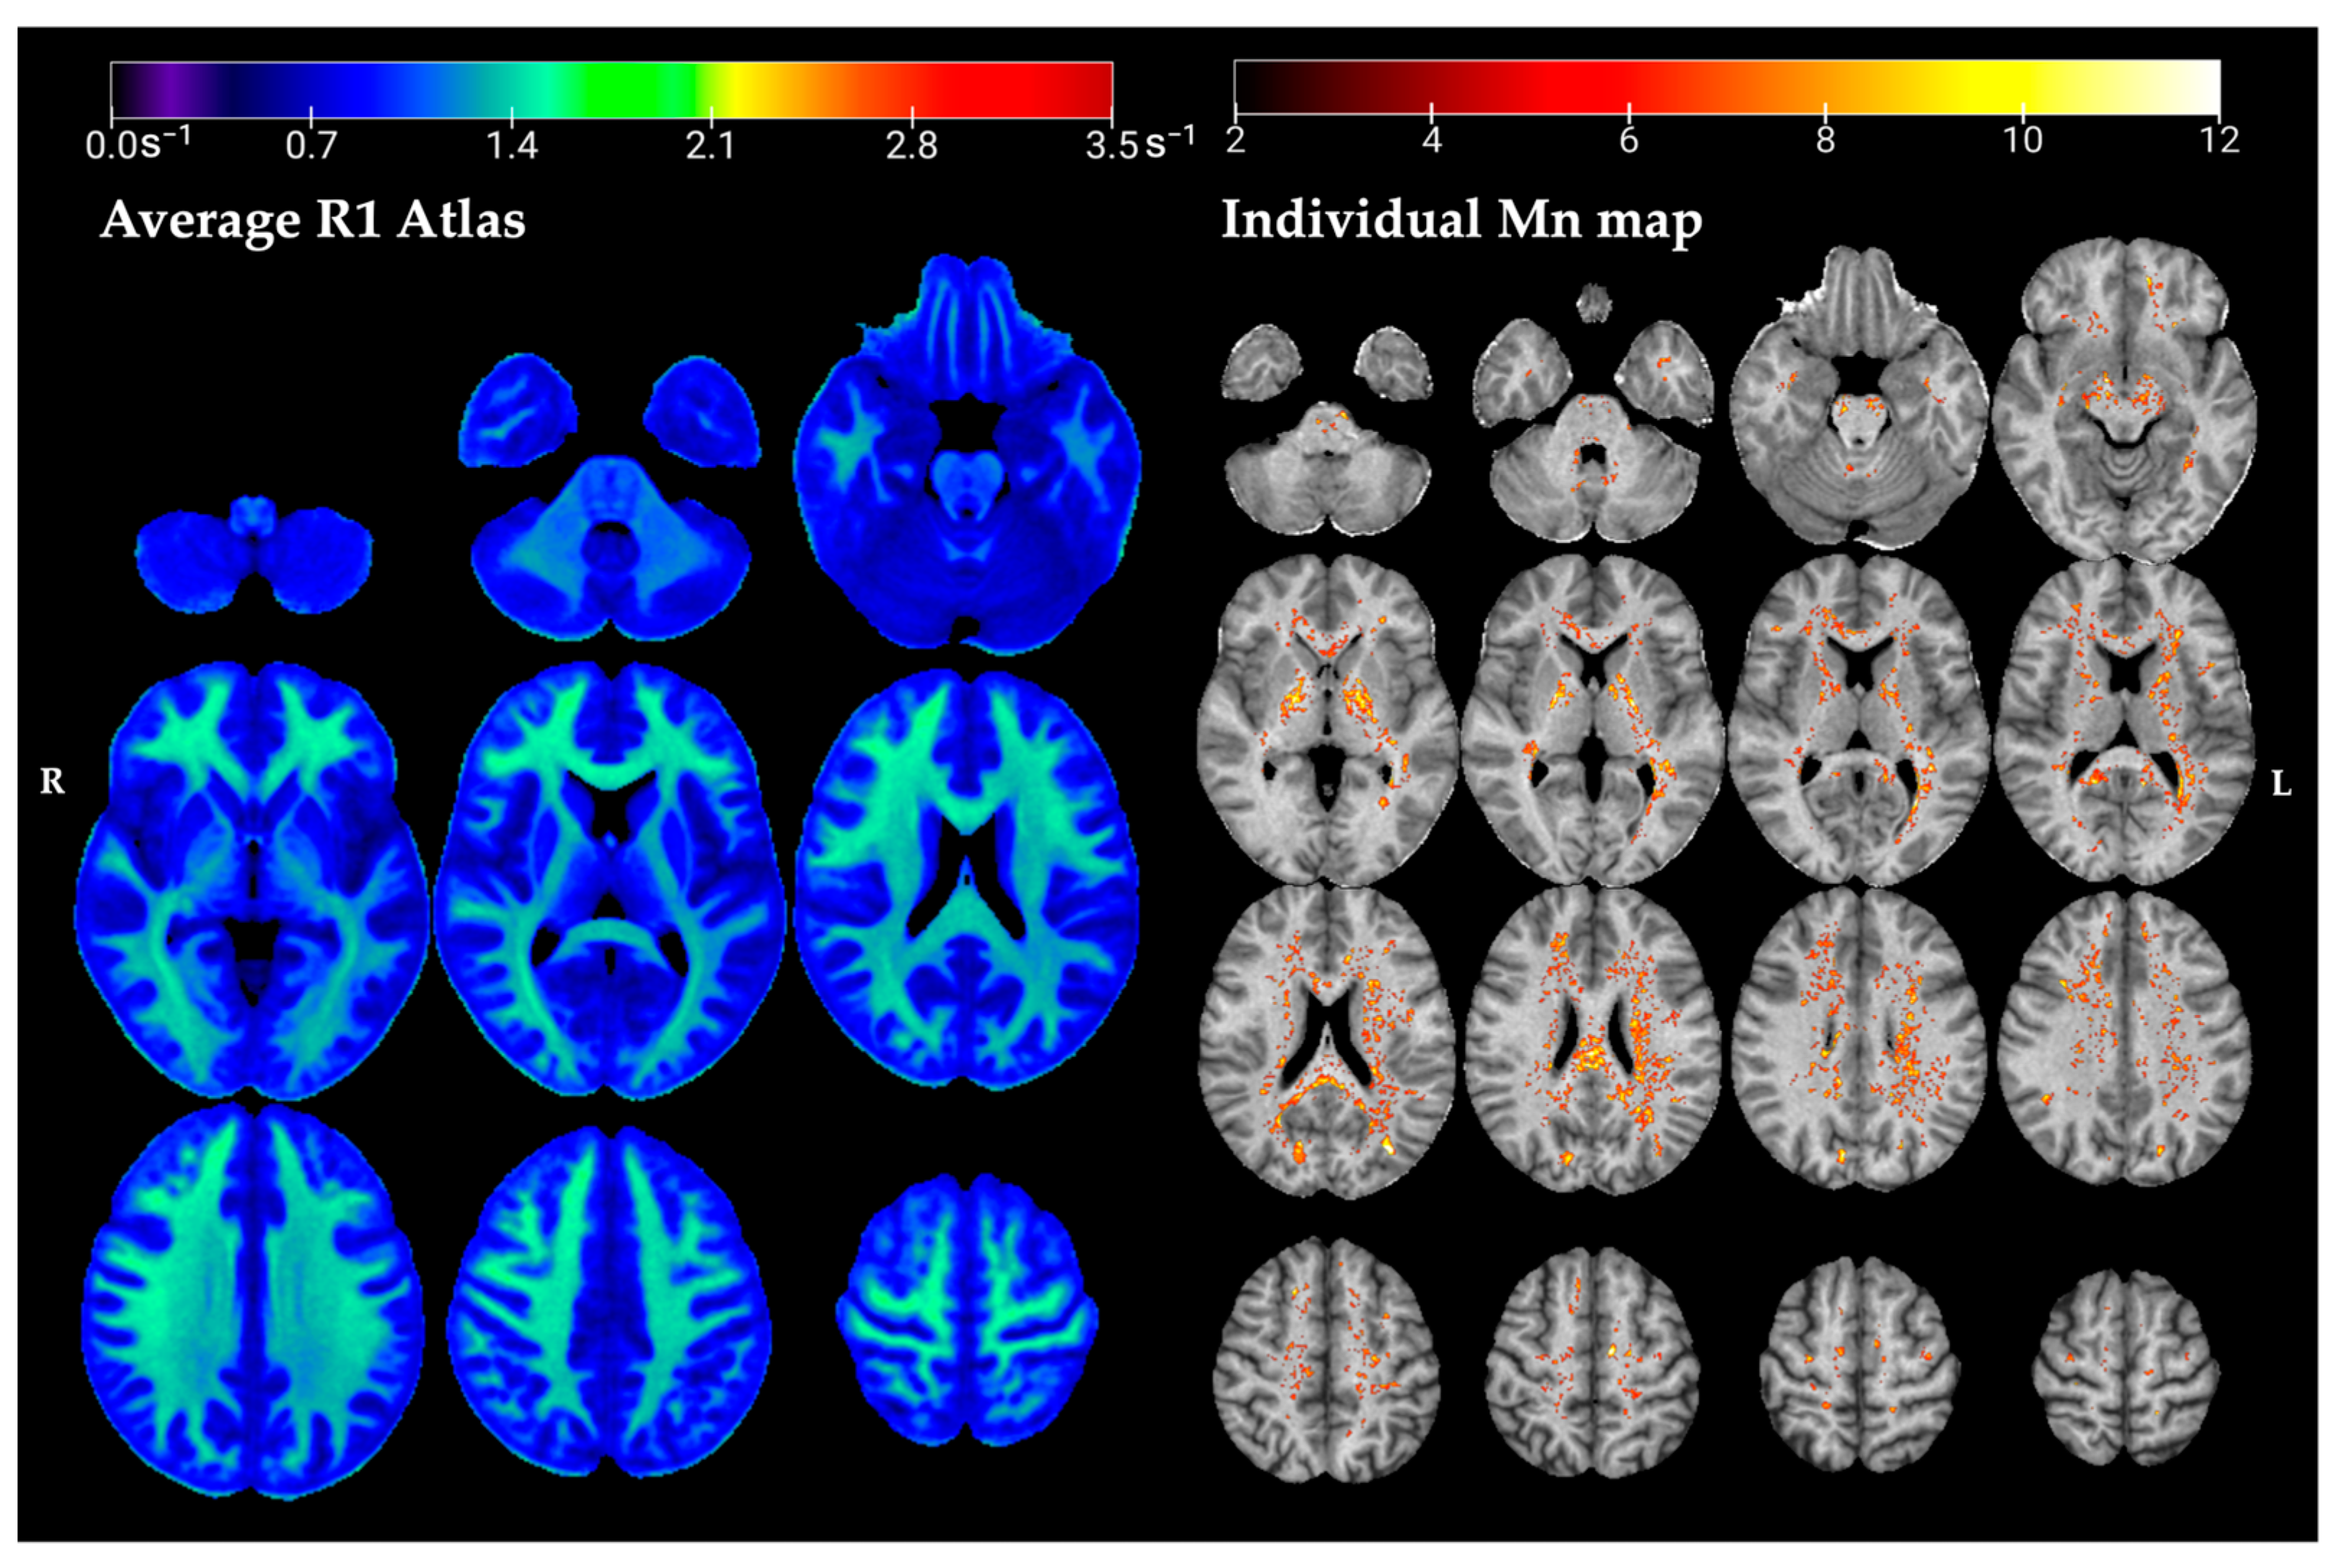

2.4. R1 Normative Atlas

2.5. Single-Subject Comparison

3.1. R1 Atlas